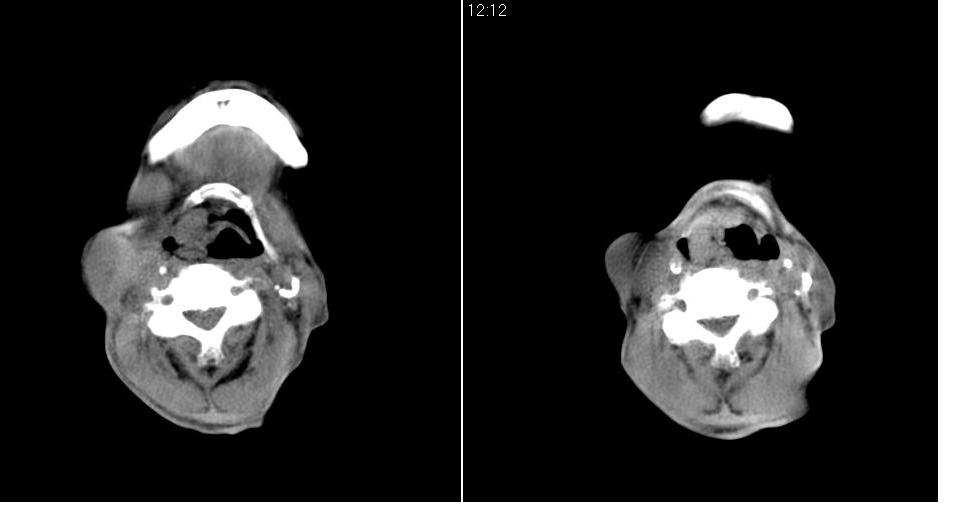

男 70岁,右侧颈部包块八个月余,下午及夜间疼痛加剧,包块质硬。化验穿刺镜下可见大量成堆裸核上皮细胞,可符合结核性淋巴结炎。

右侧颈部不规则软组织密度肿块影,密度均,边缘不清,颈筋膜间隙闭塞,向内致口喉咽受压变形,外达胸锁乳突肌深部,与之分界不清,周围骨质未见异常。

病灶广泛呈浸润性生长,提示恶性病变。楼主已经指明是结核了,谢谢。

病灶广泛呈浸润性生长,与周围组织关系模糊不清,提示恶性病变可能性较大。但楼主已经指明是结核了。